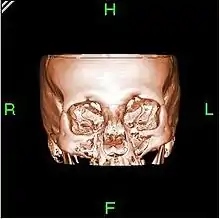

A partir de todas esas imágenes transversales (axiales), un computador reconstruye una imagen bidimensional que permite ver secciones de la pierna (o el objeto de estudio) desde cualquier ángulo. Los equipos modernos permiten incluso hacer reconstrucciones tridimensionales. Estas reconstrucciones son muy útiles en determinadas circunstancias, pero no se emplean en todos los estudios, como podría parecer. Esto es así debido a que el manejo de imágenes tridimensionales no deja de tener sus inconvenientes.

Un ejemplo de imagen tridimensional es la imagen 'real'. Como casi todos los cuerpos son opacos, la interposición de casi cualquier cuerpo entre el observador y el objeto que se desea examinar hace que la visión de este se vea obstaculizada. La representación de las imágenes tridimensionales sería inútil si no fuera posible lograr que cualquier tipo de densidad que se elija no se vea representada, con lo que determinados tejidos se comportan como transparentes. Aun así, para ver completamente un órgano determinado es necesario mirarlo desde diversos ángulos o hacer girar la imagen. Pero incluso entonces veríamos su superficie, no su interior. Para ver su interior debemos hacerlo a través de una imagen de corte asociada al volumen y aun así parte del interior no siempre sería visible. Por esa razón, en general, es más útil estudiar una a una todas las imágenes consecutivas de una secuencia de cortes que recurrir a reconstrucciones en bloque de volúmenes, aunque a primera vista sean más espectaculares.